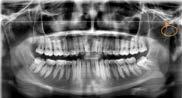

En la radiografía lateral de cráneo ( Figura 6 ) se ve la línea estética de Rickets, que el labio superior se encuentra a +0.5 mm y el inferior a -2 mm. En las mediciones cefalométricas más importantes en la figura 11 un ANB de 5º, GoGn-SN de 33º y FMA de 21º crecimiento normodivergente y Witts de -1 mm. A los criterios dentales encontramos

1-PLT de 129º e IMPA 99º proinclinación de incisivos tanto superiores como inferiores. En la radiografía panorámica (Figura 7), la presencia de 32 órganos dentarios, con terceros molares inferiores aún sin erupcionar y terceros molares superiores

7. Radiografía panorámica.

Panorámicas de inicio a fin (Figura 16) el paralelismo radicular, genera estabilidad a largo plazo en el tratamiento. Se extrajeron los terceros molares para eliminar discrepancia posterior y lograr adecuada

Figura 16. Radiografías panorámicas. a) Inicio. b) Progreso. c) Final.

distalización. Se alineo la curva de Spee acetuada y se libero correctamente el apiñamiento dental que presentaba el paciente al inicio del tratamiento.